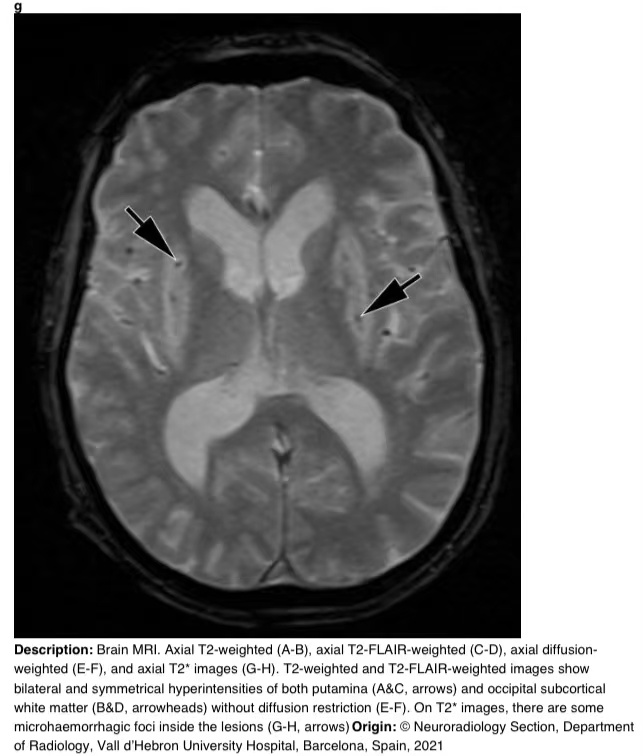

在16天的随访中,脑部MRI显示壳核和枕下皮质下白质上对称的T2/FLAIR高信号。T2图像显示病变内有微出血(图3)。

图3g

图3 a-h 脑部核磁共振成像。轴向T2加权(A-B)、轴向T2 FLAIR加权(C-D)、轴向弥散加权(E-F)和轴向T2图像(G-H)。T2加权和T2 FLAIR加权图像显示双侧和对称的壳核高信号(A和C,箭头)和枕下皮质下白质高信号(B和D,箭头),无弥散限制(E-F)。在T2图像上,病变内有一些微出血病灶(G-H,箭头)。